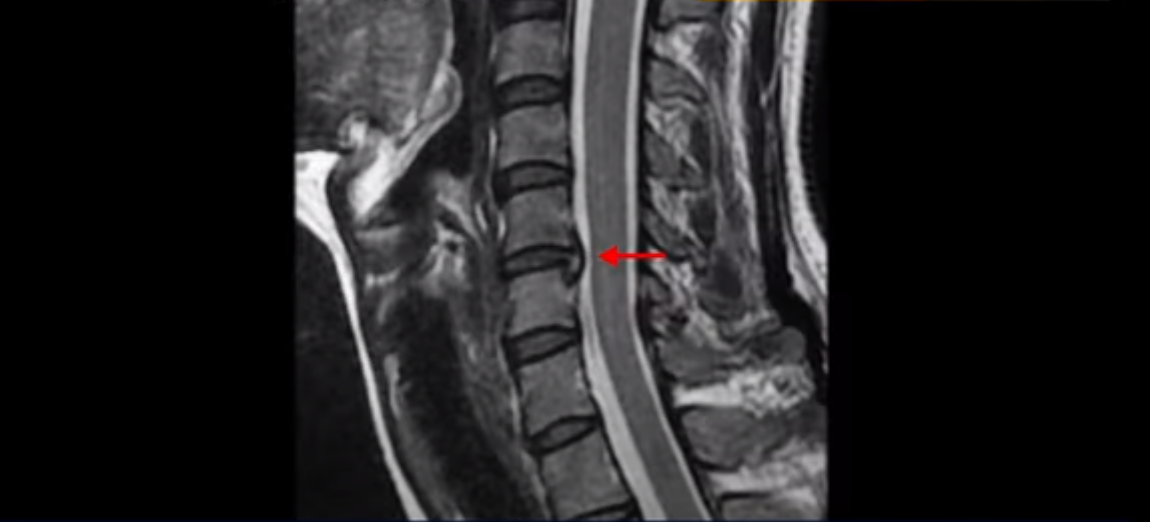

이런 목 형태를 가지면 목이 안 아플 수가 없습니다. 그리고 목에 엄청난 부담을 주기 때문에 디스크가 퇴행되면서 찢어질 가능성이 높아지죠. 이 환자분은 오른쪽과 왼쪽이 모두 저리고 아픕니다. MRI를 보면 5번 6번 디스크가 오른쪽 파열되어 아래로 흘러내려가 있습니다.

더 윗마디 3번 4번을 보면 왼쪽으로 디스크가 밀려나가 있습니다.

그래서 양쪽 어깨와 팔이 다 저리고 아픈 겁니다. 이런 신경이 눌리고 자극되는 목디스크가 왜 우리는 치료가 허리디스크보다 훨씬 더 쉽고 빠르다고 얘기하는 걸까요? 허리에 비해 입원치료 기간이 반 정도로 짧아서 평균 2주 정도 걸립니다. 참고로 이 환자분은 통원치료로 딱 8번 받은 후 이 후기를 찍으셨습니다. 목디스크가 비수술치료 성공률이 높고 빠른 이유는 목이 무게, 즉 하중을 허리에 비해 굉장히 적게 받기 때문 입니다. 그래서 여러분이 만일 수술을 고민하고 있다면, 또 신경주사가 안 듣는다면 정말로 안 해볼 이유가 없는 치료입니다.